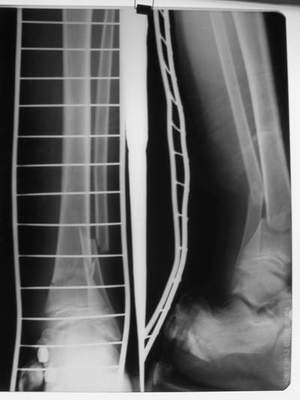

A> Это сросшийся перелом малоберцовой кости. И ложный сустав

A> н\3 б\берцовой кости.

Нашел в комп-ре схожий случай:

1) з/репозиция, 2) фиксация 2 спицами, 3) аппарат, 4) фиксационные

спицы удалены...